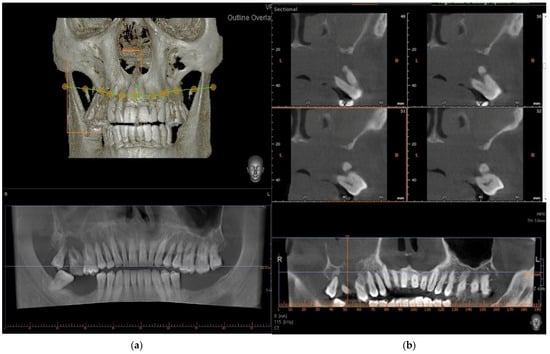

2. Case Presentation